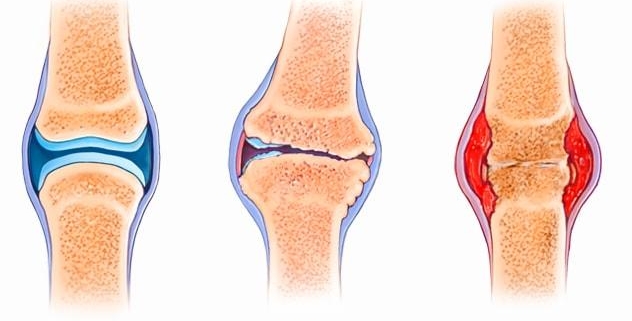

Osteoarthritis, informally known as wear-and-tear arthritis, is a common chronic condition of the joints. It occurs when the cartilage that cushions the ends of bones in your joints gradually erodes. This degenerative joint disease affects millions of people worldwide, making it one of the most prevalent forms of arthritis. As osteoarthritis progresses, it can result in severe joint pain and limit mobility, significantly impacting a person’s quality of life.

Osteoarthritis can be classified into two categories: primary and secondary. The former is typically associated with aging and is attributed to the natural wear and tear of the joints. On the other hand, secondary osteoarthritis is caused by an underlying condition or disease, such as obesity or injury, that damages the cartilage.

Symptoms

Osteoarthritis symptoms often develop slowly and worsen over time. Common symptoms include:

– Joint pain during or after movement

– Tenderness when light pressure is applied to the joint

– Stiffness, particularly upon waking up or after being inactive

– Loss of flexibility in a joint

– Grating sensation or cracking sound when a joint is used

– Bone spurs, which are extra bits of bone that form around the affected joint

– Swelling in a joint